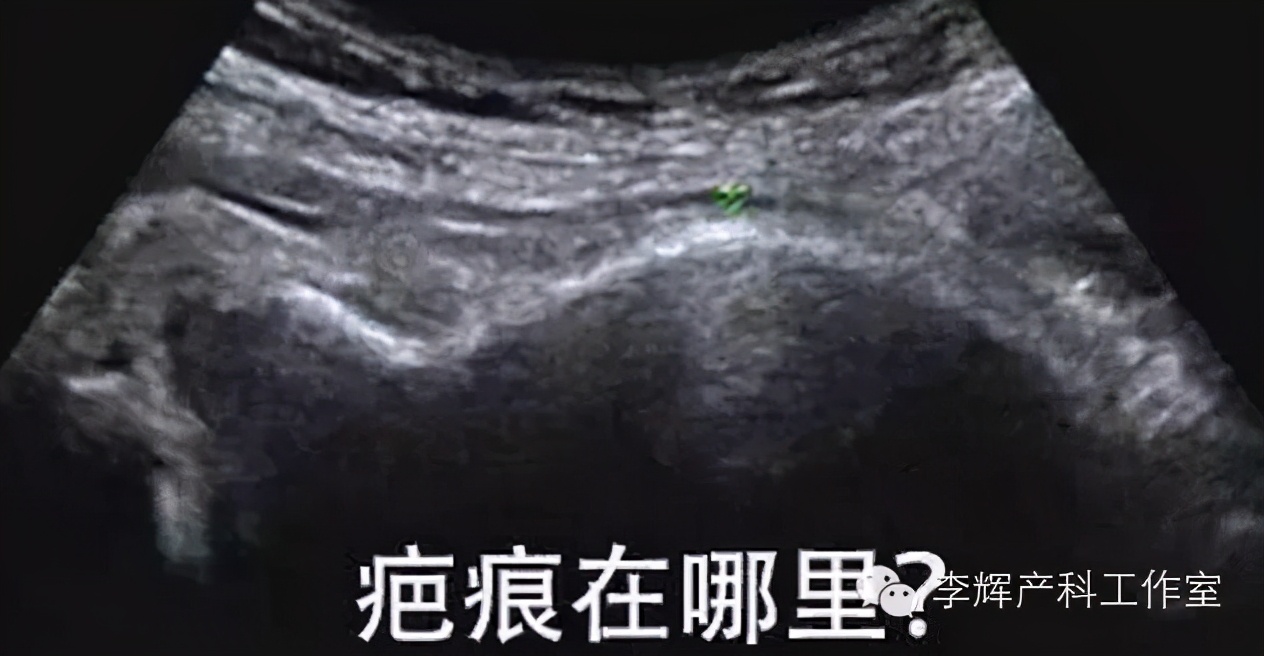

另外,对于剖宫产术后瘢痕的监测,一定不要迷信去超声下看瘢痕的厚度,纠结是2mm容易破裂还是3mm容易破裂,单纯根据疤痕厚度测量来判断是否有破裂风险是不正确的,科学依据不足。超声测量下的几毫米误差太容易,瘢痕子宫是否破裂要取决于子宫瘢痕的弹性而非厚度,弹性根本无法进行产前评估。如果妊娠过程中没有瘢痕切口的撕裂疼痛感和瘢痕处的压痛几很少有破裂的。因此,不要强迫超声科医生去看瘢痕厚度,超声医生常常抱怨受此困扰。除非患者有症状,当超声检查提示子宫瘢痕处回声有连续性中断时,我会很慎重对待,不排除有不全子宫破裂可能。中山大学附属一院@超女style的微博里发了一篇微博,测的瘢痕是0mm,她评论妊娠结局为没有发生子宫破裂,我懂她想表达的意思,没有去问术中所见,但产科临床医生会判定为“不全子宫破裂-即瘢痕断裂,但浆膜层完整”。这种情况下产科医生会根据孕周、是否存在宫缩和是否存在切口压痛等症状综合判定再次进行剖宫产手术时间。